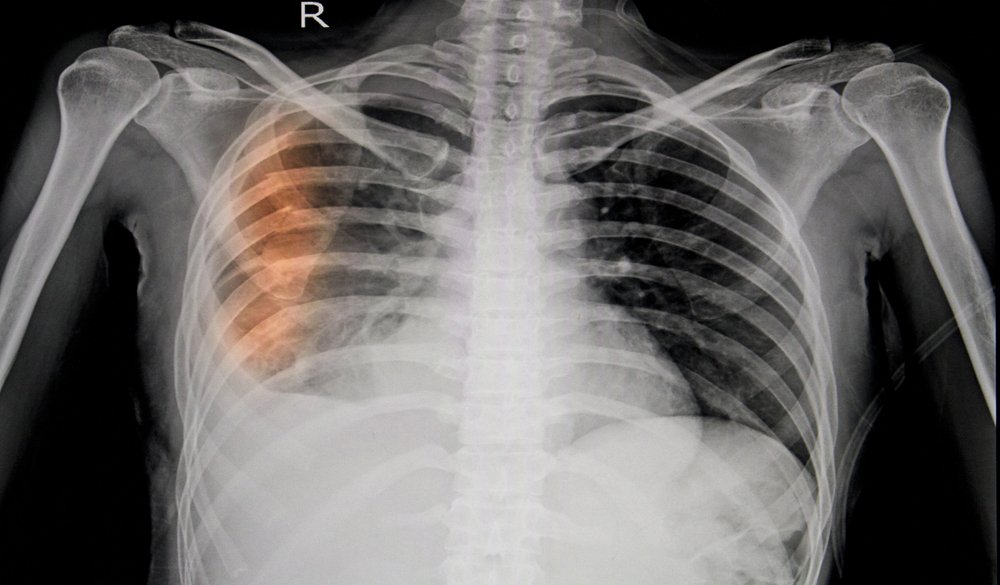

Although many broken ribs can be treated with rest and recuperation, the medical attention necessary to diagnose them can be expensive. The cost of doctor’s visits, x-rays, and other related medical treatment often comes as an unpleasant financial surprise to people with broken ribs.